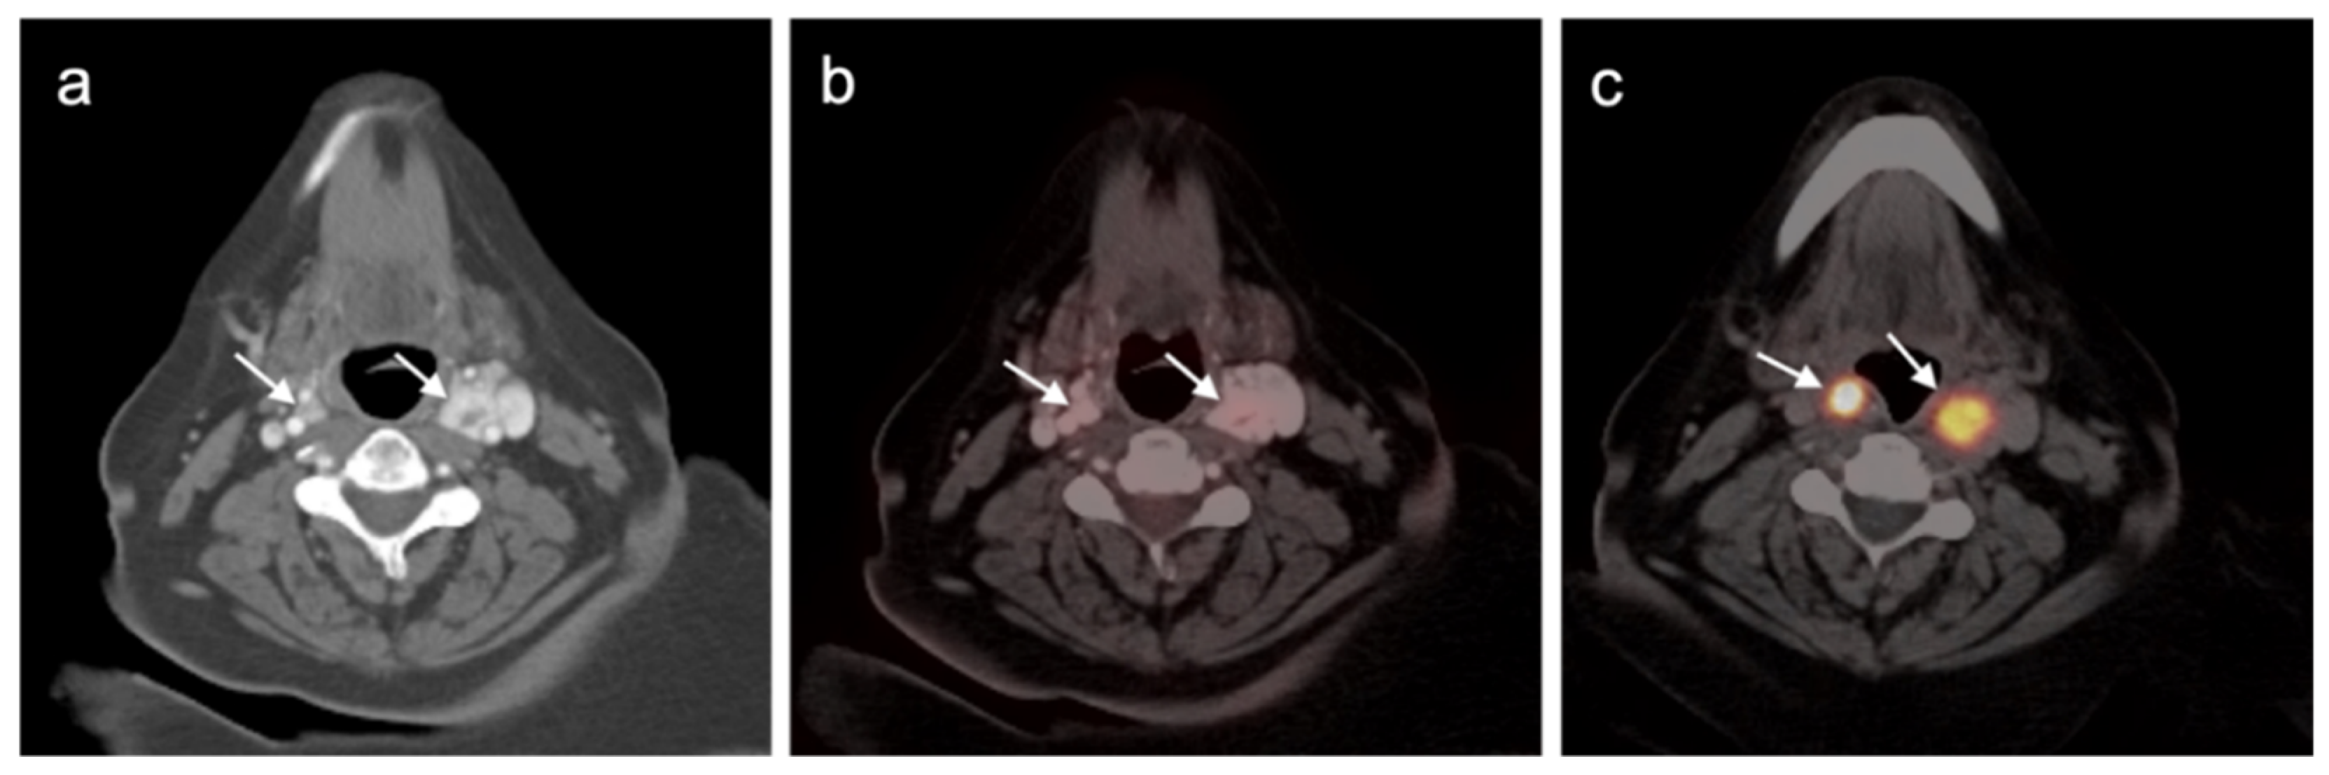

4.5. Pheochromocytoma and Paraganglioma